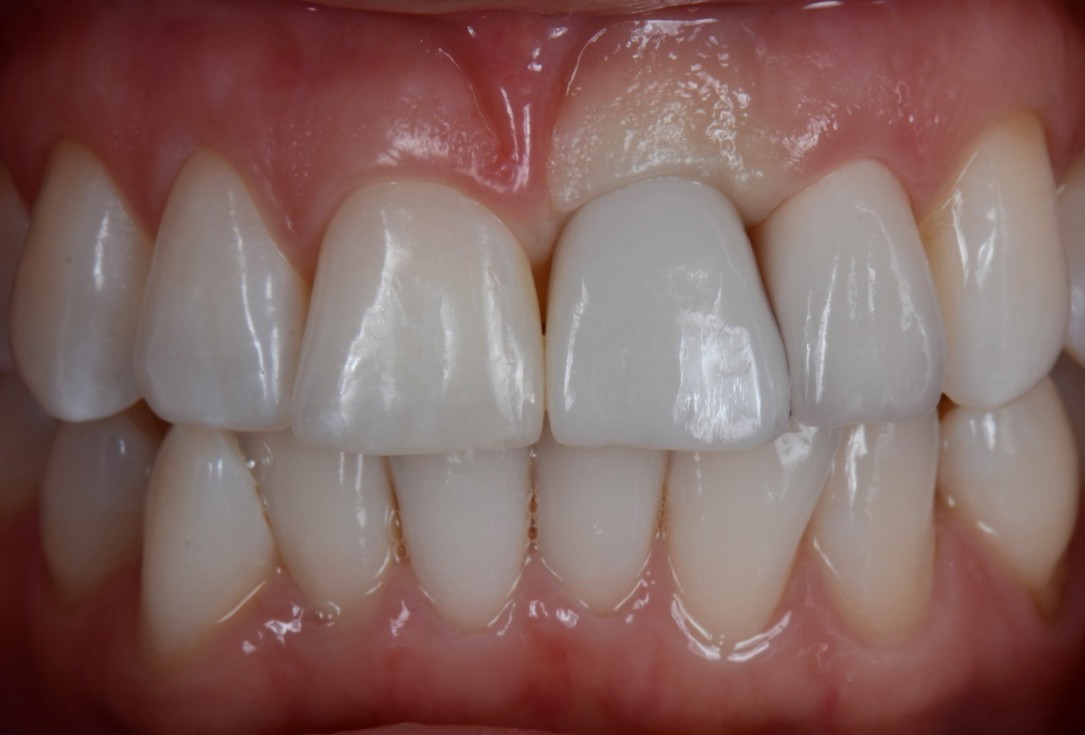

16/16 - Final prosthetic restoration

Socket preservation with cerabone® - Dr. R. A. Nader